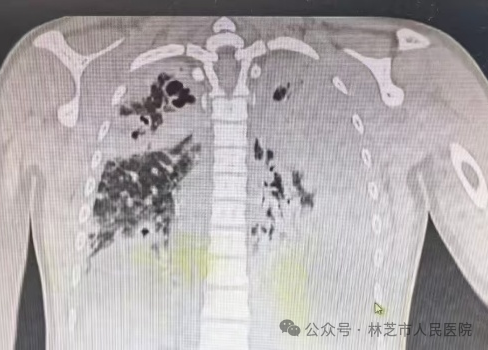

入院后胸部CT:重症肺炎